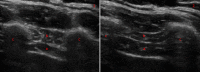

Fig. 4

Diaphragm thickness in B-mode thoracic view at end expiration (1) and inspiration (2) in a heathy volunteer. The diaphragm can be seen between two echogenic layers (a) with the intercostal compartment above (b). The two muscle layers sit between two ribs (c)